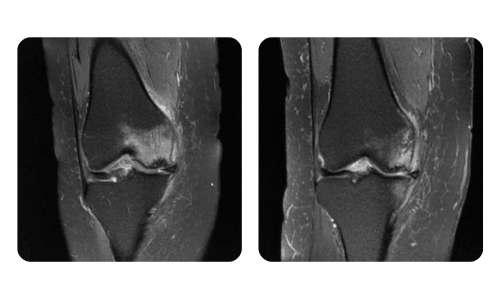

I progressi dei nostri pazienti, misurati prima e dopo la terapia iperbarica, riflettono l'efficacia e l'impatto positivo del trattamento. Scopri i risultati documentati della terapia iperbarica presso la clinica Hyperbarium Oradea, basati su valutazioni cliniche e dati oggettivi che evidenziano miglioramenti significativi in diverse condizioni.